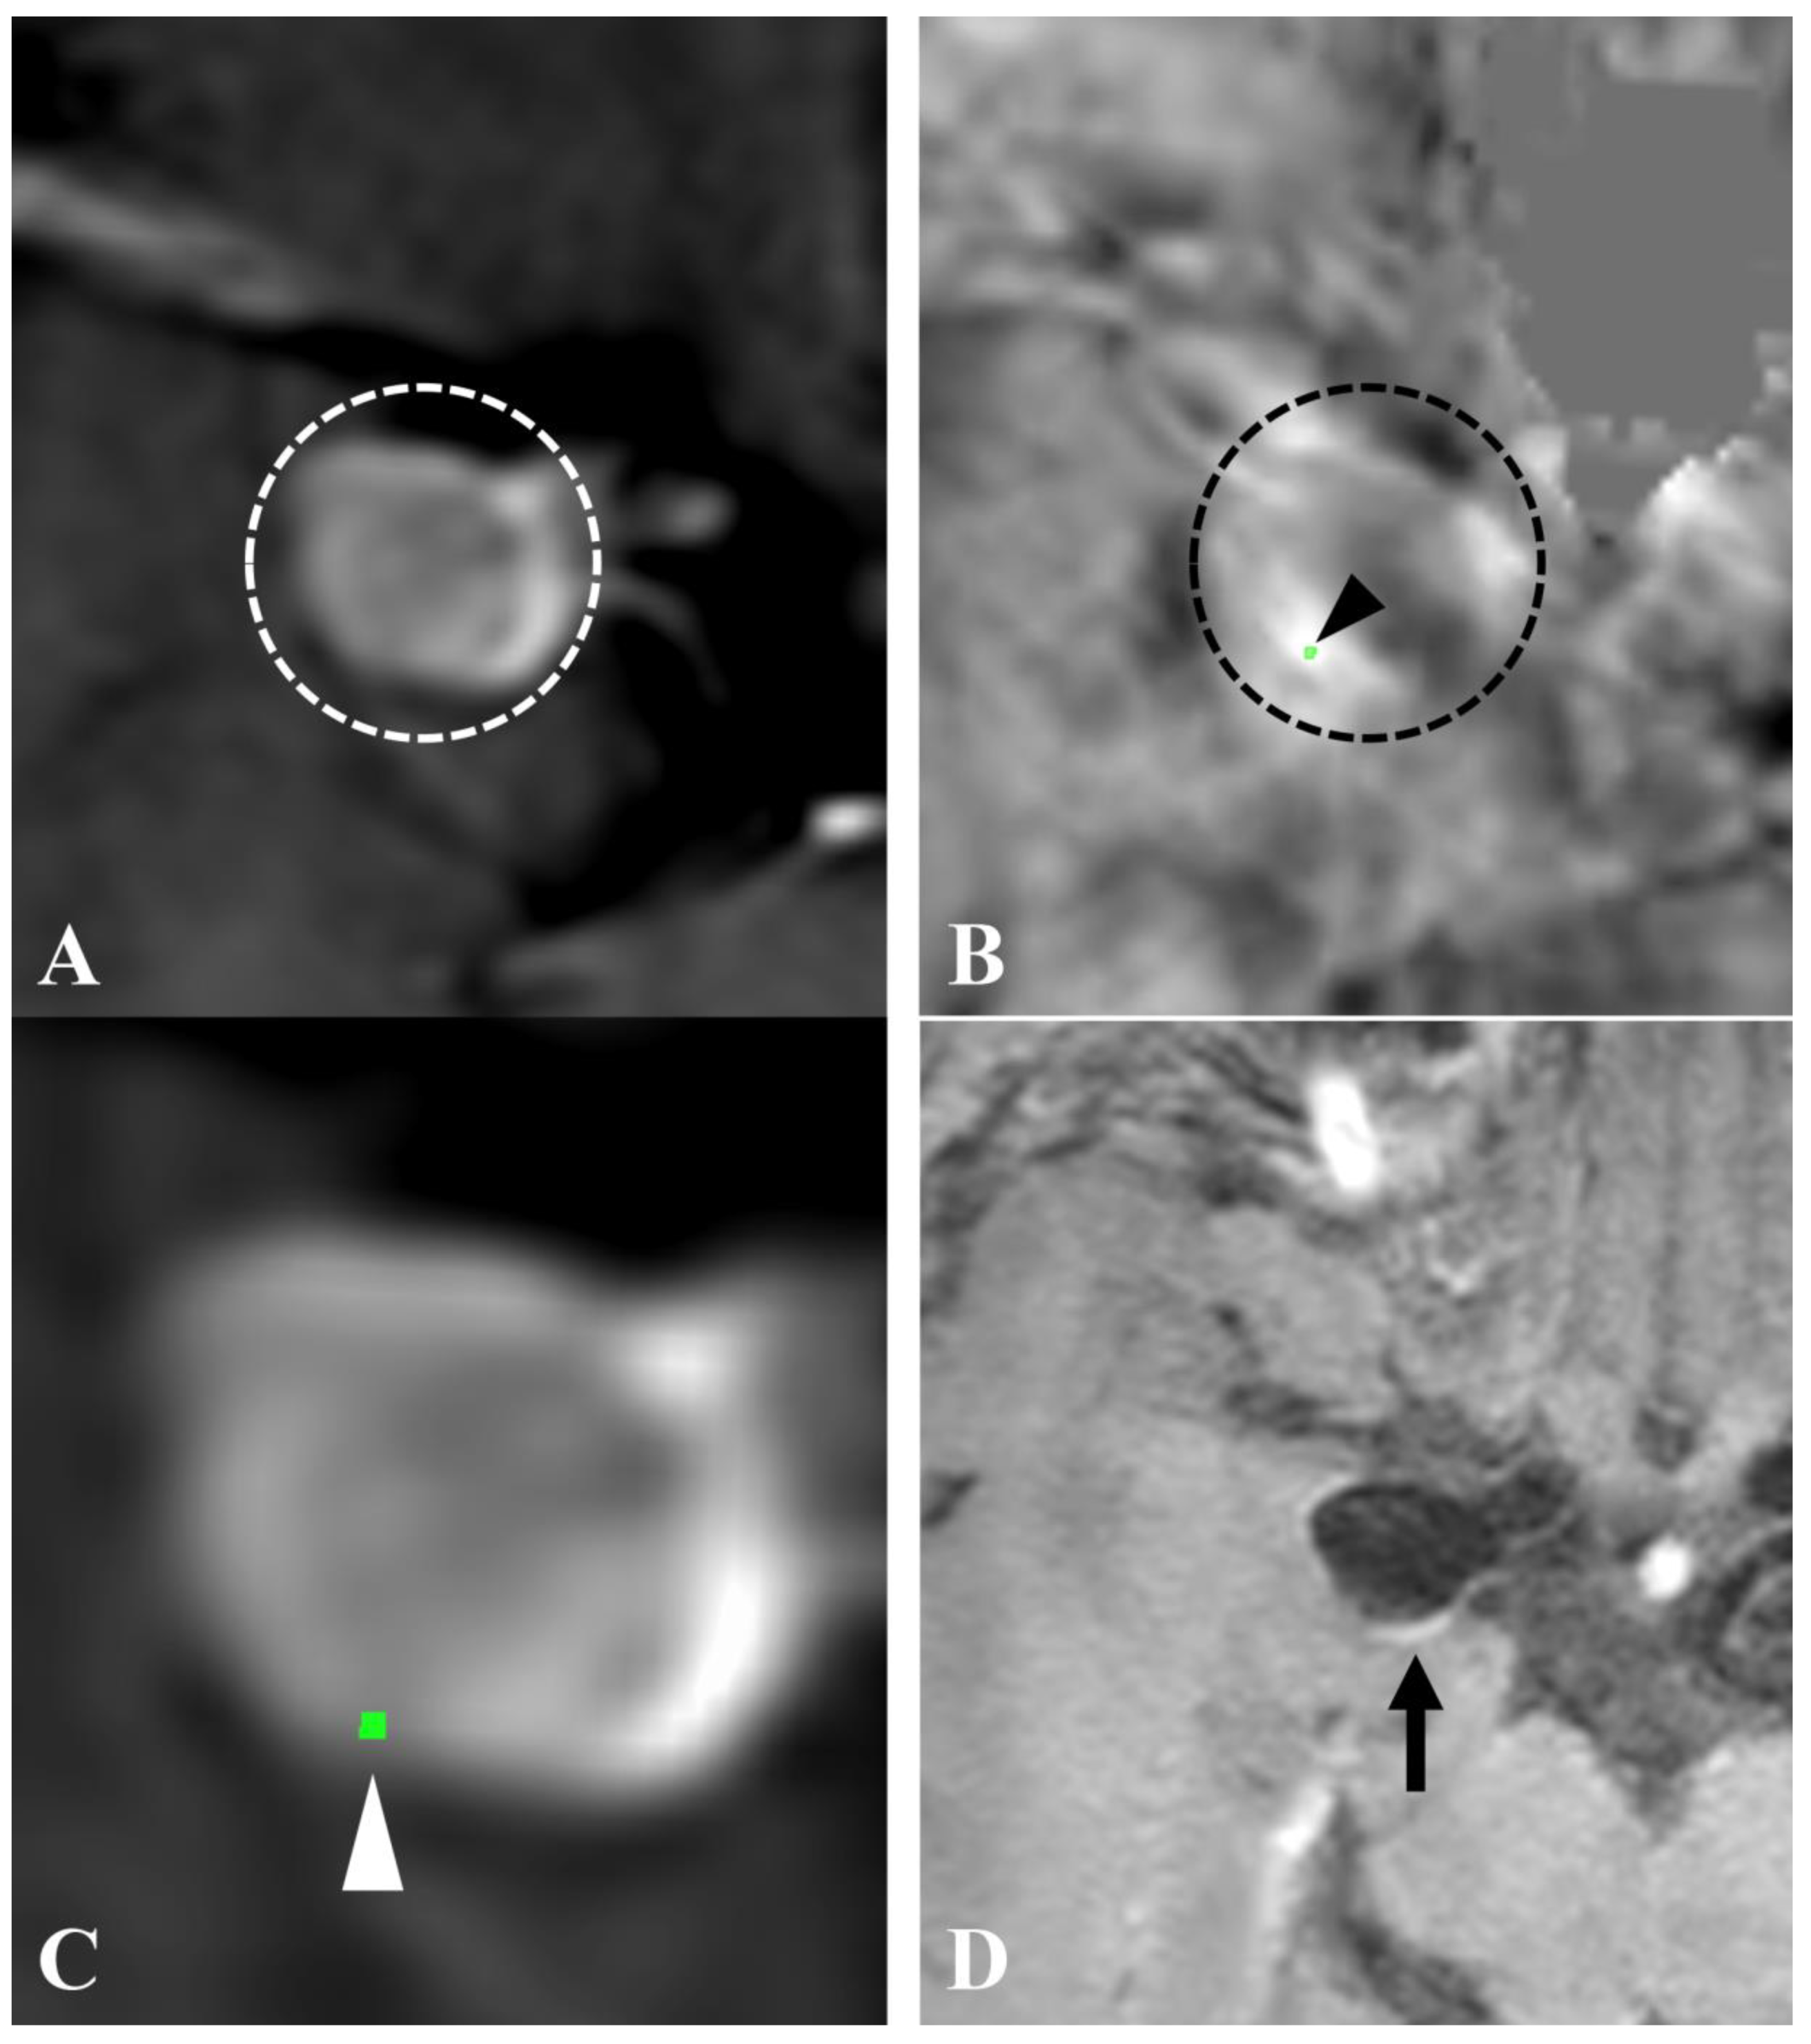

- Nakagawa, D.; Kudo, K.; Awe, O.; Zanaty, M.; Nagahama, Y.; Cushing, C.; Magnotta, V.; Hayakawa, M.; Allan, L.; Greenlee, J.; et al. Detection of microbleeds associated with sentinel headache using MRI quantitative susceptibility mapping: Pilot study. J. Neurosurg. 2018, 130, 1391–1397. [Google Scholar] [CrossRef]